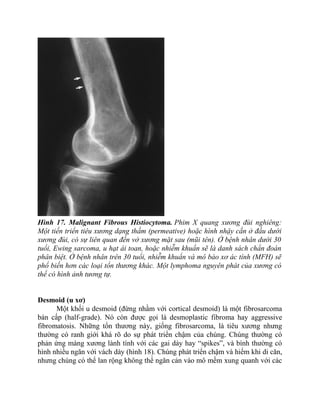

Hình 17. Malignant Fibrous Histiocytoma. Phim X quang xương đùi nghiêng:

Một tiến triển tiêu xương dạng thấm (permeative) hoặc hình nhậy cắn ở đầu dưới

xương đùi, có sự liên quan đến vở xương mặt sau (mũi tên). Ở bệnh nhân dưới 30

tuổi, Ewing sarcoma, u hạt ái toan, hoặc nhiễm khuẩn sẽ là danh sách chẩn đoán

phân biệt. Ở bệnh nhân trên 30 tuổi, nhiễm khuẩn và mô bào xơ ác tính (MFH) sẽ

phổ biến hơn các loại tổn thương khác. Một lymphoma nguyên phát của xương có

thể có hình ảnh tương tự.